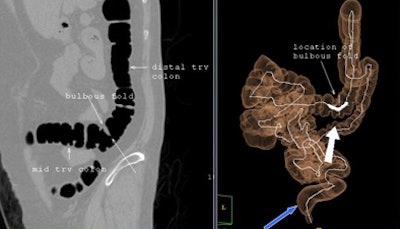

![]() |

| A woman with prior hysterectomy and incomplete colonoscopy demonstrates tortuous colon anatomy, including a bulbous fold, and a redundant sigmoid colon that has prolapsed into the pelvic inlet, preventing the endoscopist from advancing the colonoscope. |

"What is the cause of this increased rate of incomplete or failed colonoscopy in women following hysterectomy? Is it due to sigmoid angulation, is it tethering and adhesions and redundant colon? We're not really sure," Zafar said. "These are issues for further study."

For example, the group has not yet compared colonic anatomy in patients with hysterectomy versus no hysterectomy, Zafar said in response to a question from the audience. "Some of these women have incredibly tortuous colons, not just the sigmoid colon," she said. "We need to go back and look."